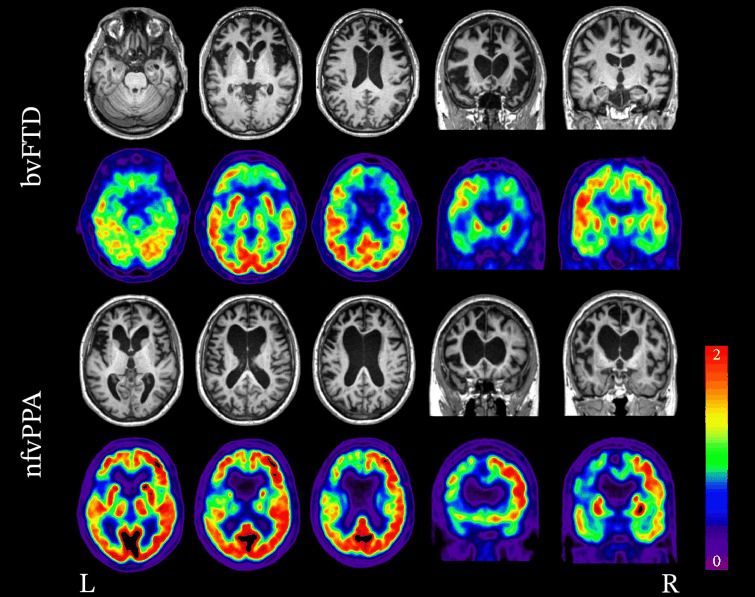

Coronal T1-weighted MRI (a, b) and fused FDG-PET MRI (c) in a patient with semantic dementia

Bhogal P et al. Eur Radiol 23, 3405-17 (2013); used with permission